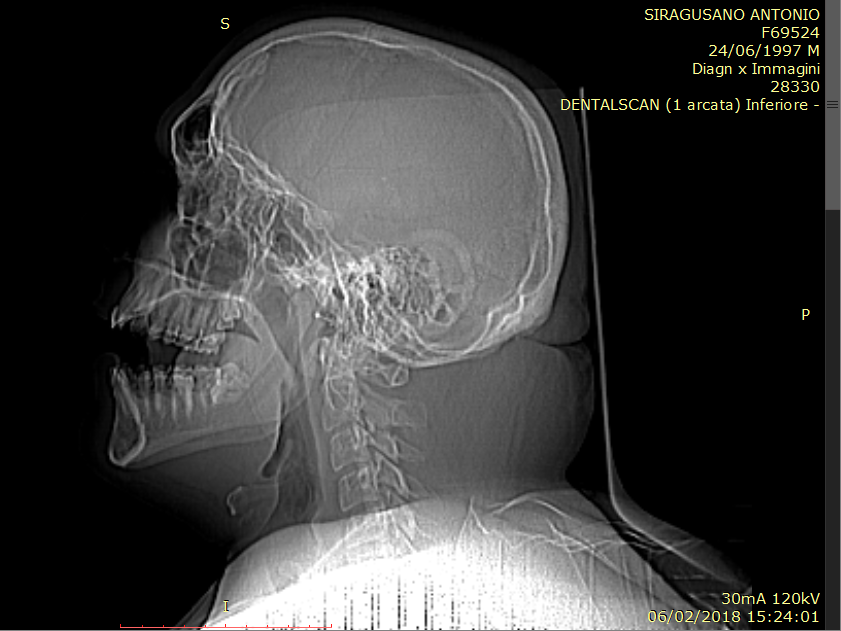

in questi giorni ho dovuto effettuare un dentalscan per rimuovere due ottavi inclusi. Tra i referti c'è pure la mia tc cranio, quindi mi chiedevo se potreste dare un'occhiata e dirmi in caso se ci sia qualcosa di sospetto ed è quindi necessario consultare uno specialista. Grazie anticipatamente

Immagine.png

[ 263.26 KiB | Osservato 1128 volte ]